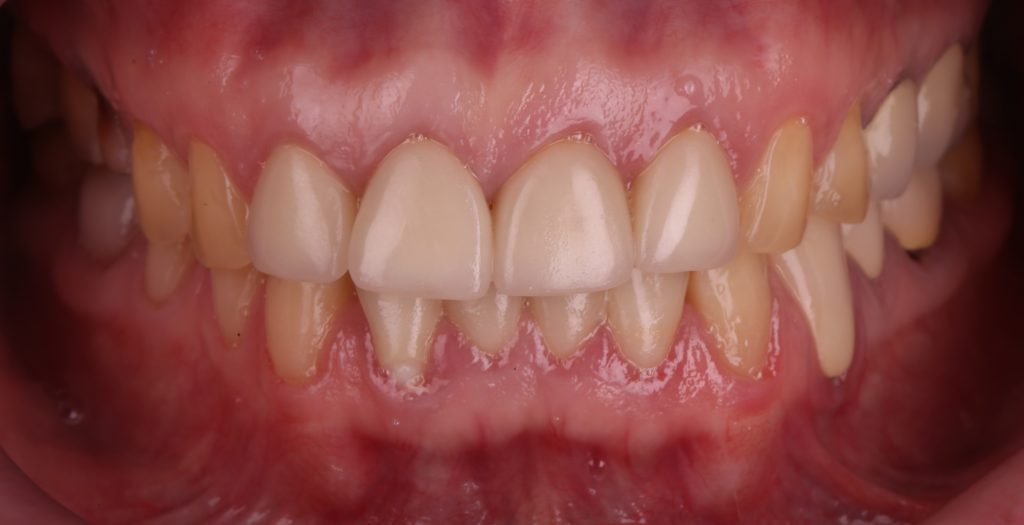

Пациентка обратилась с жалобами на неудовлетворительную эстетику зубных рядов. Выполнен полный диагностический комплекс, включающий КЛКТ исследование

Итоговый результат комплексной ортопедической реабилитации вместе с Diagnocat AI